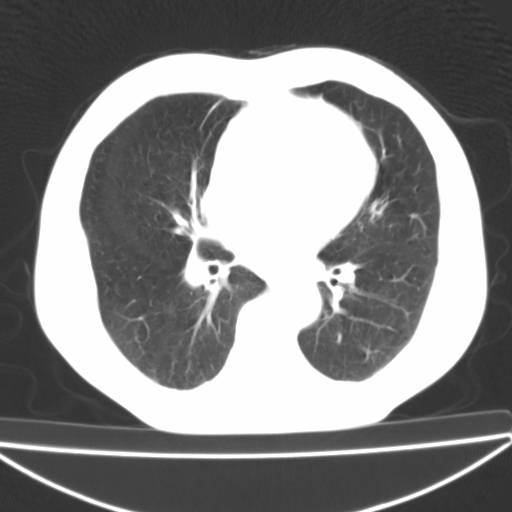

以下是引用zjzjr在2006-12-6 19:04:00的发言:[br]左肺上叶尖后段可见椭圆形高密度影,其内可见点状钙化影,周围可见卫星病灶.首先考虑结核,双侧少量胸腔积液.

以下是引用李世军在2006-12-6 19:54:00的发言:[br]左肺上叶尖后段可见椭圆形高密度影,其内可见点状钙化影,周围可见卫星病灶.首先考虑结核,双侧少量胸腔积液. [br] [br] 双肺轻度肺气肿,左肺上叶后段见多发斑片状密度增高影,周围见少许斑点状卫星病灶,双侧胸膜增厚粘连,纵隔内未见明显改变,考虑结核可能性大,请结合临床或增强扫描. [br] [br]

以下是引用13081830109在2006-12-6 19:35:00的发言:[br]左肺上叶尖后段可见椭圆形高密度影,其内可见点状钙化影,周围可见卫星病灶.首先考虑结核,双侧少量胸腔积液.